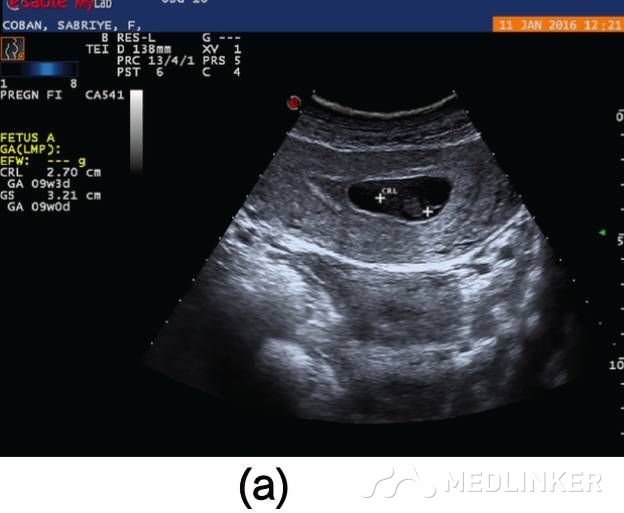

图1 (a)刮宫术前彩超示: 宫内死胎, 妊娠9周, 未见子宫动静脉瘘;(b)子宫前壁可见大小60×60×56mm(103cm3)杂乱回声区, 并延伸至子 宫左侧 ;(c)彩色多普勒超声检查示极丰富“五彩镶嵌”彩色血流

患者入院诊断:动静脉畸形。介入科会诊后行双侧子宫动脉栓塞术,栓塞材料为氰丙烯酸丁酯和碘油的混合物。该患者栓塞前后情况如图2所示。子宫动脉栓塞术后,患者未出现并发症,术后2天,患者出院,血hCG降至1766mIU/mL。术后1个月复查超声,未见血流,且受损范围缩小至61∗46∗52mm(77cm3)(图3),血hCG<0.5mIU/mL。  图2(a)右/左髂内子宫动脉造影术示:轻度扩张的子宫动脉显影浑浊,子宫内见多血管性肿块;(b)双侧子宫动脉栓塞术后图像   图3(a)2个月后的阴式超声示::受损范围缩小至61∗46∗52mm(77cm3);(b)多普勒彩超未见血流              根据年龄、生育要求、病变位置及范围大小选择不同的治疗方案,AVM主要的治疗方法是子宫切除和子宫动脉栓塞。育龄期有生育要求的子宫动静脉瘘患者首选治疗方法是子宫动脉栓塞,但是其远期的安全性尚存争议,而且行子宫动脉栓塞术后,妊娠的孕妇发生胎位异常、早产、产后出血及剖宫产的风险增大。        一些学者认为保守治疗适合无症状的AVM患者;还有学者认为出血少的AVM患者可以用甲基麦角新碱、促性腺激素释放激素类似物、达那唑等治疗。总之,目前对无症状的子宫动静脉瘘的治疗暂无统一的共识。        总之,子宫动静脉瘘是比较罕见且危险的临床疾病。通常,这种疾病常见于既往发生过自然流产的年轻女性,我们应该牢记行人工流产术(吸宮术)的患者,术后可能会继发子宫动静脉瘘,同时应该注意该病与其他疾病的鉴别。